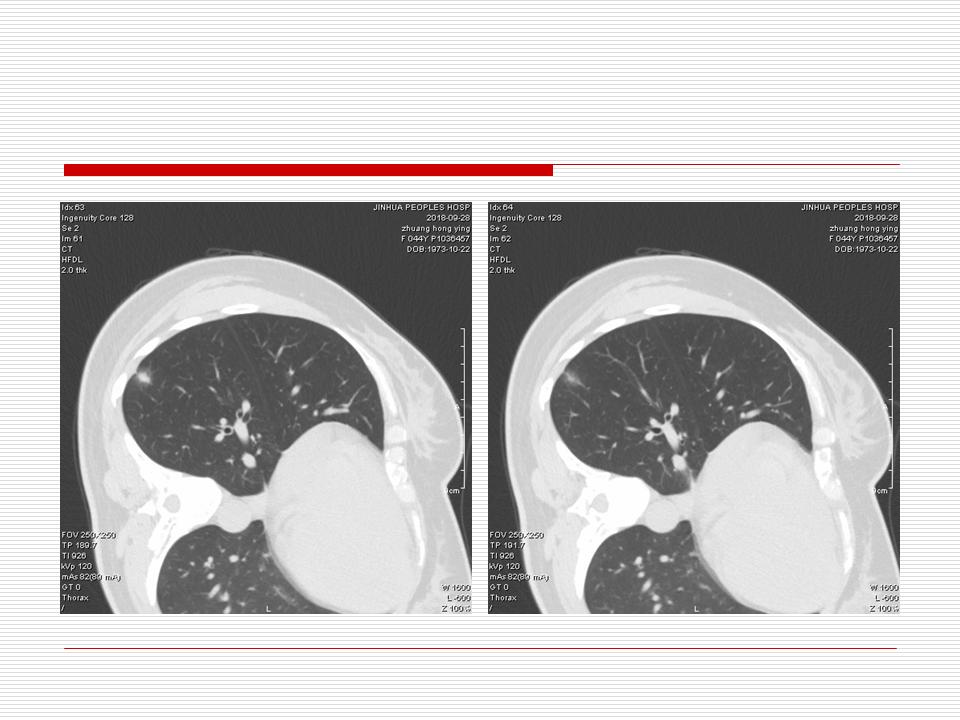

肺部阴影永恒且最重需要鉴别的是:到底是炎症还是肿瘤?但临床的病例中的影像表现难以界定或有些肿瘤特征,同时又有些炎症特点是非常常见的情况。作为临床医生我们怎么去总结分析,并找到之所以是炎症或之所以是肿瘤的细微差别或特点非常重要,也非常有用。2019.12.7浙江省2019年胸心外科学学术年会在宁波召开时,我的临床病例分析与经验总结<那些像肺癌的炎症与像炎症的肺癌>获得在大会交流的机会,以下为该PPT的内容,与你分享,希望对同道有益,有借鉴与启迪。若有探讨与进一不完善的建议,欢迎文末留言讨论: